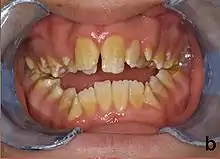

Amelogenesis imperfecta, hypoplastic type. Note the association of pitted enamel and open bite.

People with amelogenesis imperfecta may have teeth with abnormal color: yellow, brown or grey; this disorder can affect any number of teeth of both dentitions. Enamel hypoplasia manifests in a variety of ways depending on the type of AI an individual has (see below), with pitting and plane-form defects common.[4] The teeth have a higher risk for dental cavities and are hypersensitive to temperature changes as well as rapid attrition, excessive calculus deposition, and gingival hyperplasia.[5] The earliest known case of AI is in an extinct hominid species called Paranthropus robustus, with over a third of individuals displaying this condition.[6]

Type 1 - Hypoplastic

Enamel of abnormal thickness due to malfunction in enamel matrix formation. Enamel is very thin but hard & translucent, and may have random pits & grooves. Condition is of autosomal dominant, autosomal recessive, or x-linked pattern. Enamel differs in appearance from dentine radiographically as normal functional enamel.[19]